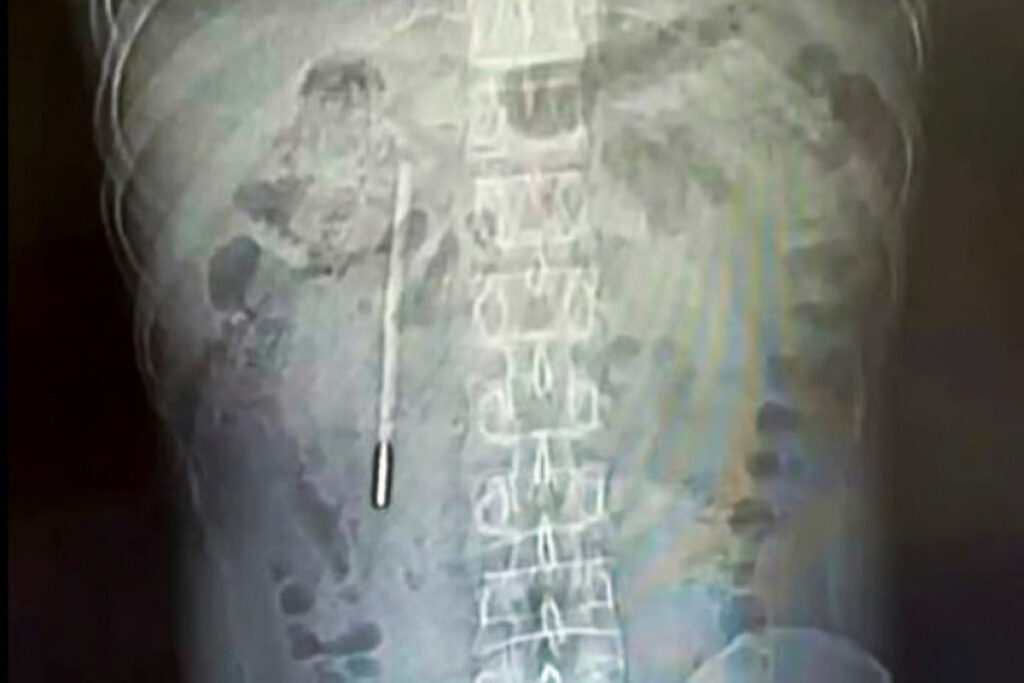

Unga ko‘ra, erkak qorin og‘rig‘i shikoyati bilan shifoxonaga murojaat qilgan. Tekshiruvlar davomida uning o‘n ikki barmoqli ichagida begona jism borligi aniqlangan. Keyinchalik ma’lum bo‘lishicha, u ushbu termometrni o‘smirlik davrida tasodifan yutib yuborgan, biroq qo‘rquv sababli bu haqda ota-onasiga aytmagan va vaqt o‘tishi bilan voqeani unutib yuborgan.

Shifokorlar termometr ichak devoriga yaqin joylashgani va teshilish hamda ichki qon ketish xavfi borligini hisobga olib, uni zudlik bilan olib tashlashgan. Tibbiy muolaja muvaffaqiyatli o‘tgan va buyum butun holatda chiqarib olingan.

Mutaxassislar qayd etishicha, termometrdagi suyuqlik hamda ko‘rsatkichlar uzoq vaqt ichida butunlay yo‘qolgan.